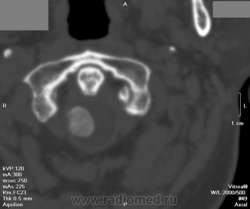

менингиома?

А знаете, вот так сразу и не сказать... "Оболочечное" расположение, гомогенное обызвествление... Наверное (осторожненько так пишу)). По крайней мере, кальцинат старый, не "злой". Такое сдавление спинного мозга - удивительны компенсаторные механизмы у человека!

Вероятнее всего менингиома.